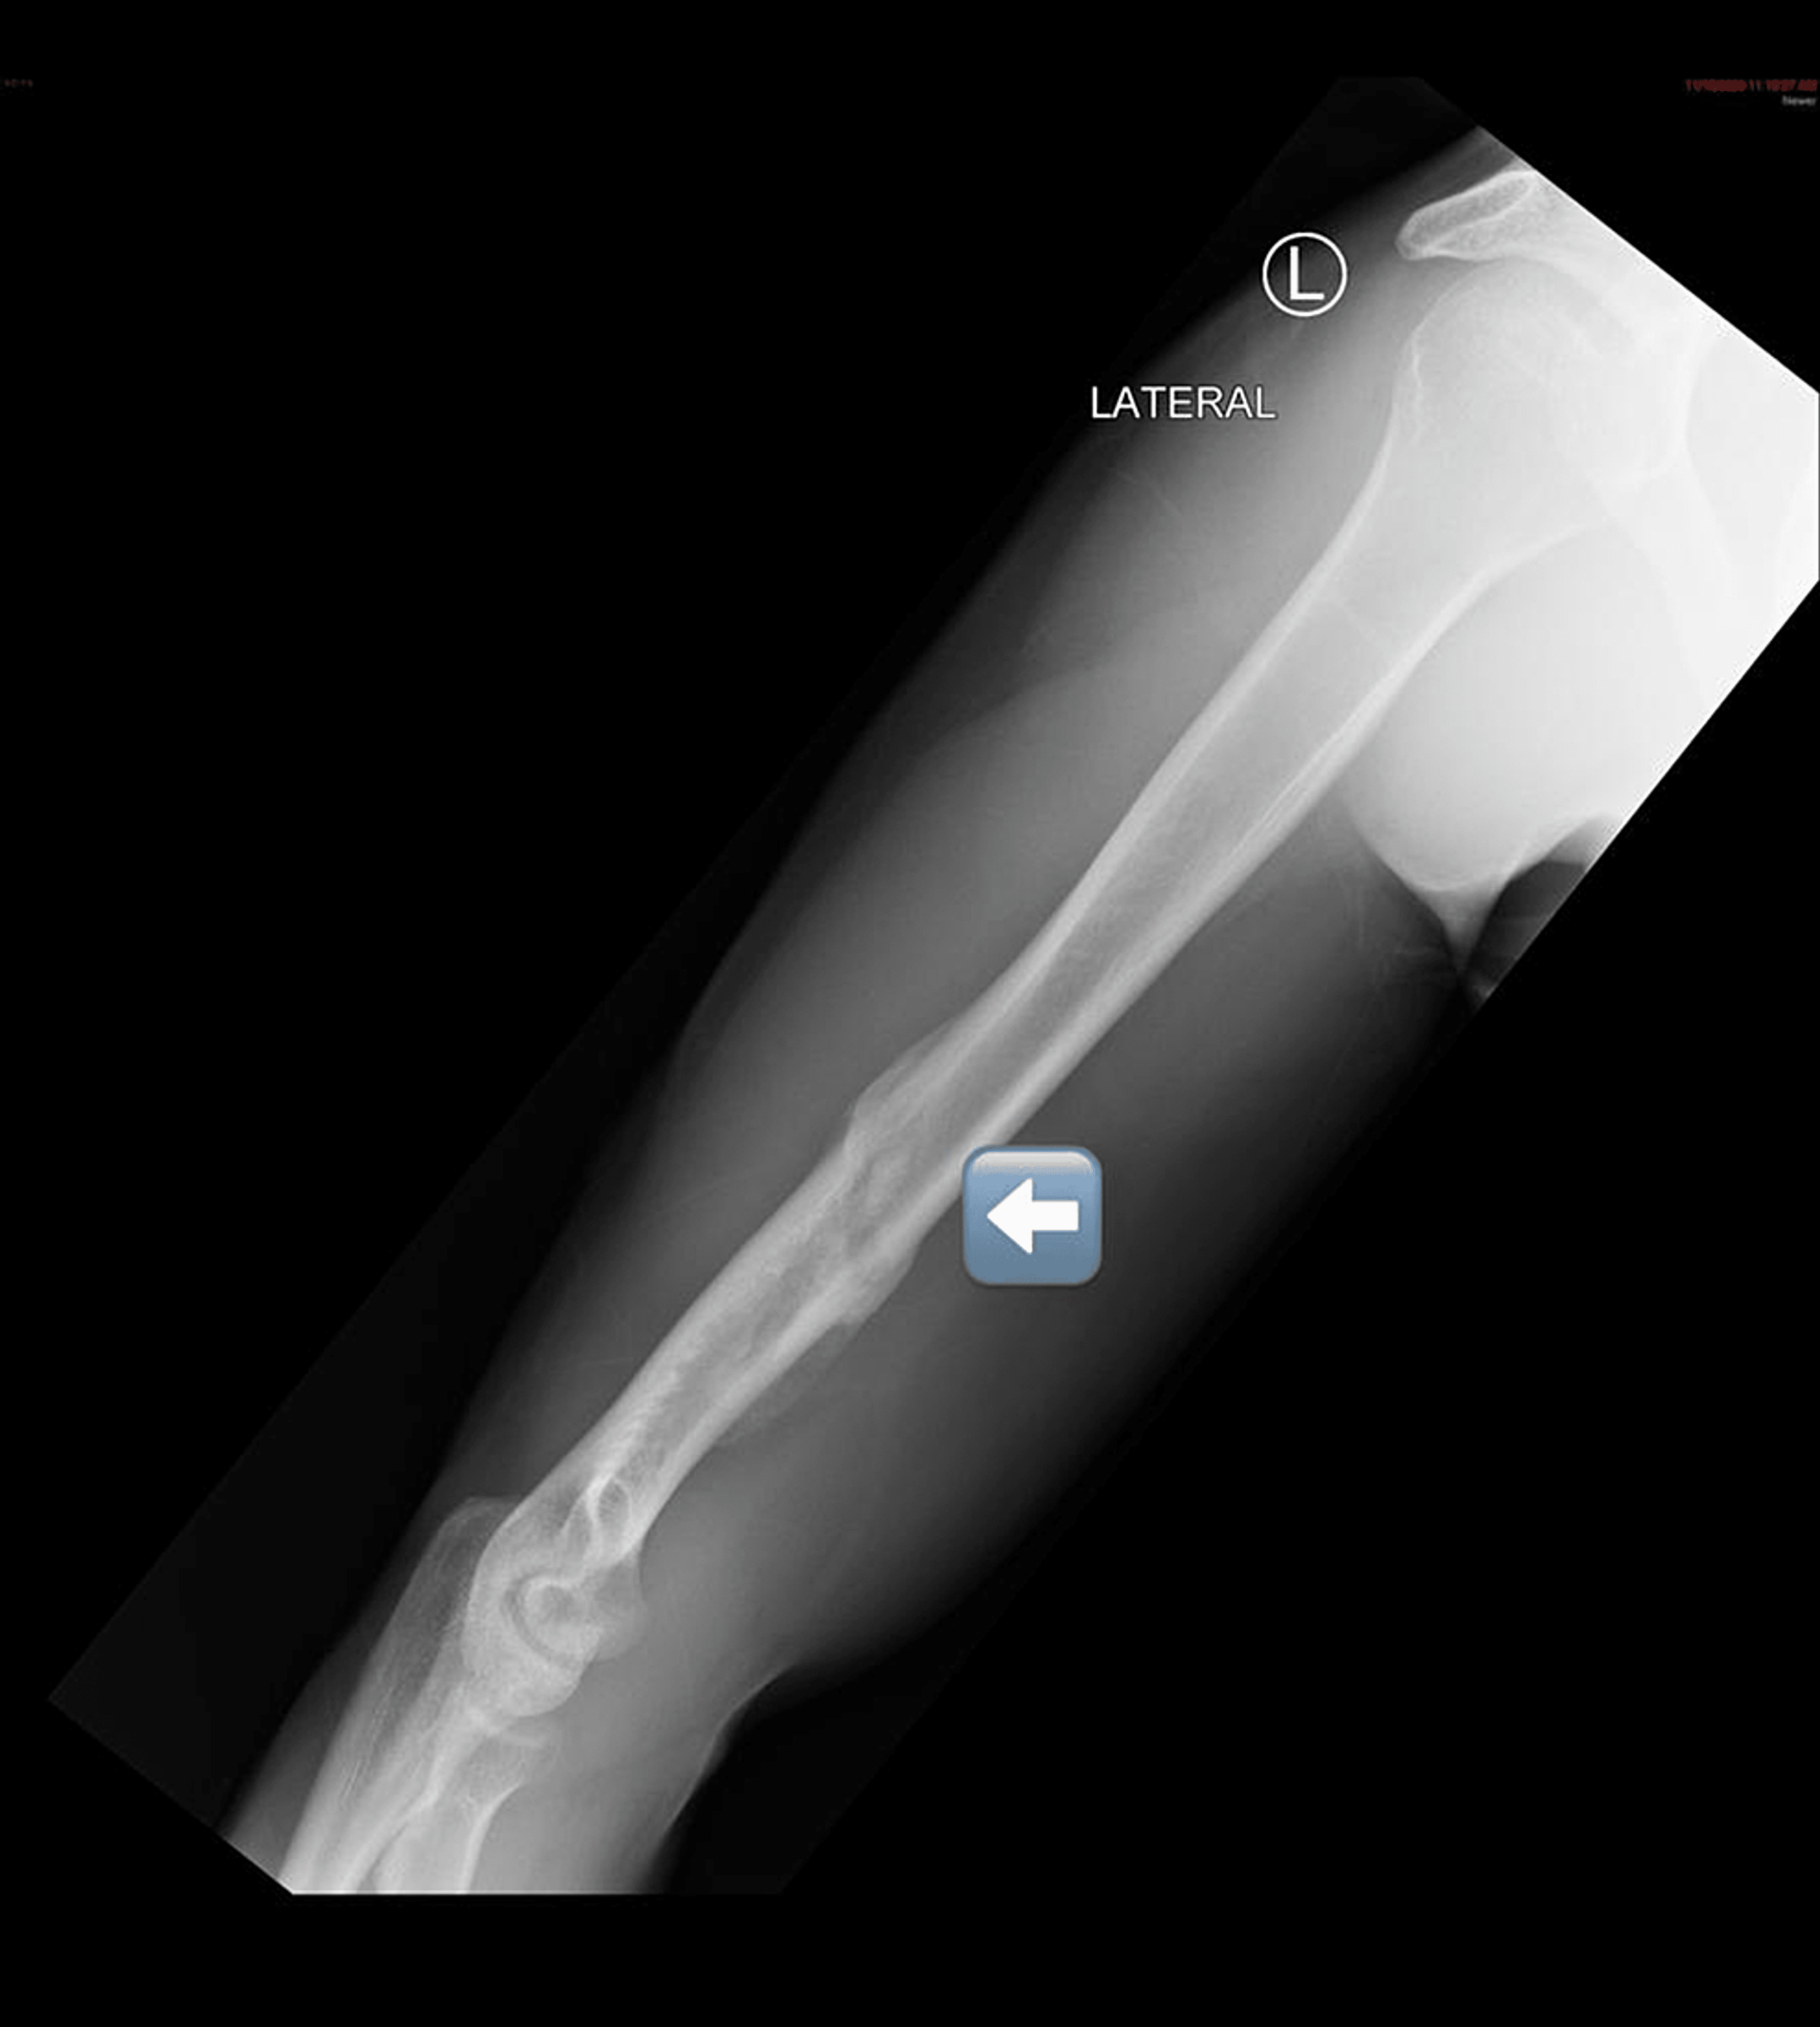

Spiral fracture, midshaft of my left humerus currently 4 weeks since Spiral Humerus Fracture Orthobullets the spiral groove, which contains the radial nerve, is located posteriorly and serves as an important landmark. They concluded that the ideal indication for functional bracing. distal humerus fractures are traumatic injuries to the elbow that comprise of supracondylar fractures, single column fractures,. pediatric humeral shaft fractures are usually traumatic in nature, although nonaccidental trauma and pathologic. Spiral Humerus Fracture Orthobullets.